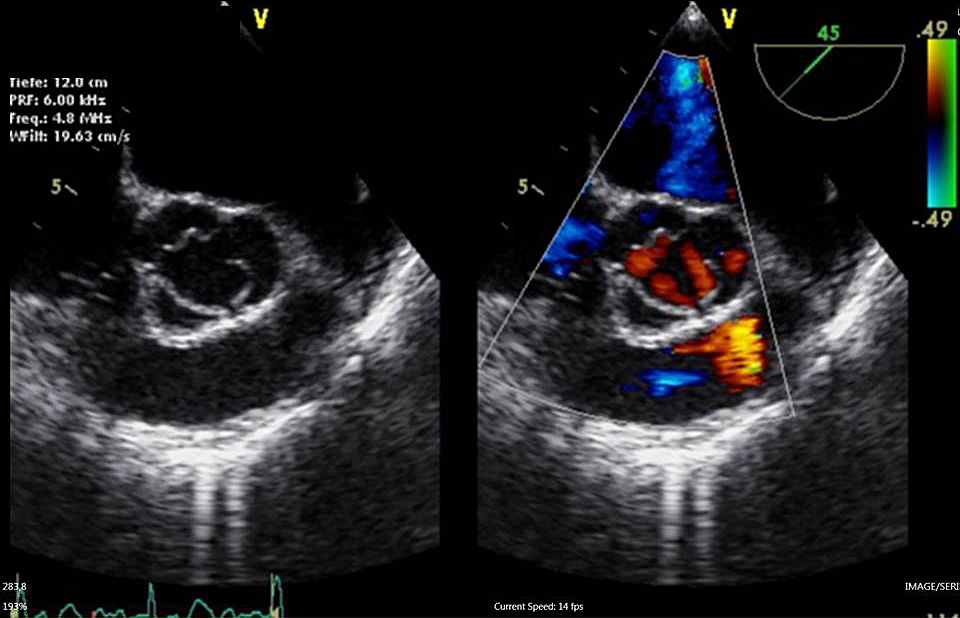

TEE

Die Transösophageale Echokardiographie ermöglicht u. a. eine sehr detaillierte Beurteilung der Herzklappen. Beispielhaft ist in der Mitte beider Abbildungen die Aortenklappe dargestellt, die aus drei Taschen besteht. Die rote und blaue Farbe markiert die Blutflussrichtung, um z. B. Undichtigkeiten (Insuffizienzen) von Herzklappen zu erkennen.